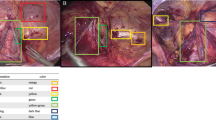

We established an image database by collecting surgical videos of 48 patients diagnosed with lumbar disc herniation, which was labeled by two spinal surgeons. We selected 6000 images of the visual field of percutaneous endoscopic spine surgery (including various tissue structures and surgical instruments), divided into the training data, validation data, and test data according to 2:1:2. We developed convolutional neural network models based on instance segmentation—Solov2, CondInst, Mask R-CNN and Yolact, and set the four network model backbone as ResNet101 and ResNet50 respectively. Mean average precision (mAP) and frames per second (FPS) were used to measure the performance of each model for classification, localization and recognition in real time, and AP (average) is used to evaluate how easily an element is detected by neural networks based on computer deep learning.

Comprehensively comparing mAP and FSP of each model for bounding box test and segmentation task for the test set of images, we found that Solov2 (ResNet101) (mAP = 73.5%, FPS = 28.9), Mask R-CNN (ResNet101) (mAP = 72.8%, FPS = 28.5) models are the most stable, with higher precision and faster image processing speed. Combining the average precision of the elements in the bounding box test and segmentation tasks in each network, the AP(average) was highest for tool 3 (bbox-0.85, segm-0.89) and lowest for tool 5 (bbox-0.63, segm-0.72) in the instrumentation, whereas in the anatomical tissue elements, the fibrosus annulus (bbox-0.68, segm-0.69) and ligamentum flavum (bbox-0.65, segm-0.62) had higher AP(average),while extra-dural fat (bbox-0.42, segm-0.44) was lowest.

Our team has developed a multi-element identification system for the visual field of percutaneous endoscopic spine surgery adapted to the interlaminar and foraminal approaches, which can identify and track anatomical tissue (nerve, ligamentum flavum, nucleus pulposus, etc.) and surgical instruments (endoscopic forceps, an high-speed diamond burr, etc.), which can be used in the future as a virtual educational tool or applied to the intraoperative real-time assistance system for spinal endoscopic operation.